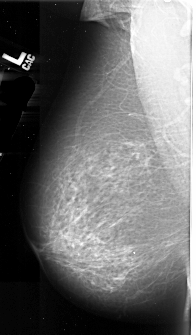

A_1009_1.RIGHT_MLO

LEFT_MLO LINES 6016 PIXELS_PER_LINE 3526 BITS_PER_PIXEL 16 RESOLUTION 42 NON_OVERLAY